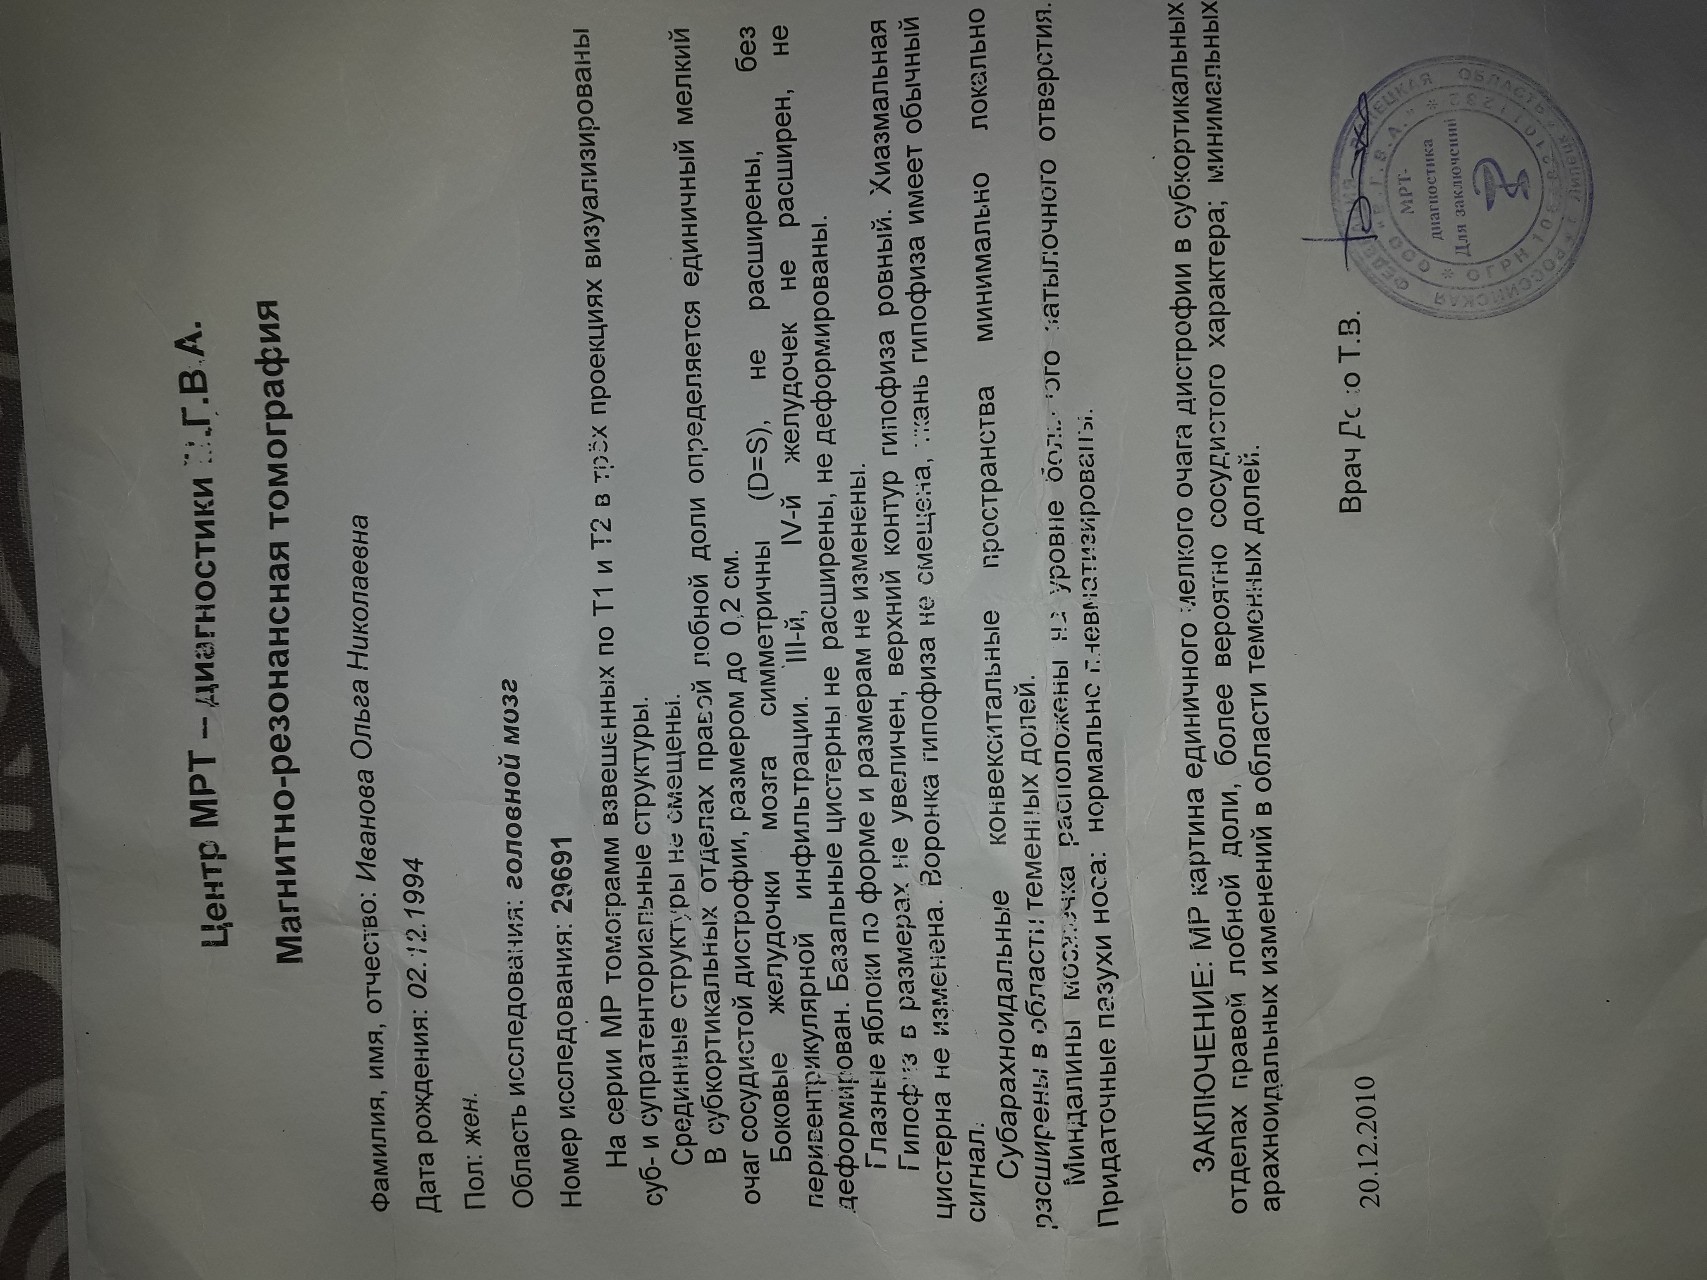

МРТ головного мозга: Расшифровка снимков и Интерпретация

Раздел: Визуальные уроки